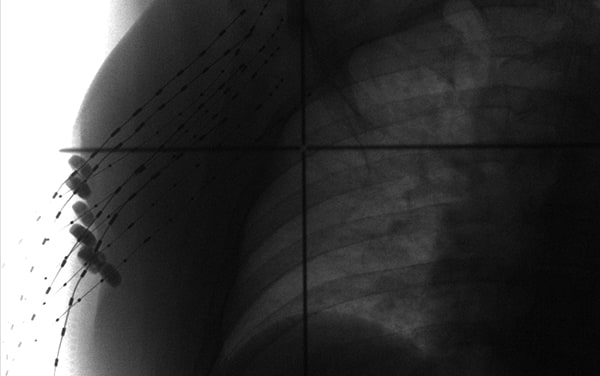

在模板的引导下,所有插植针平行植入